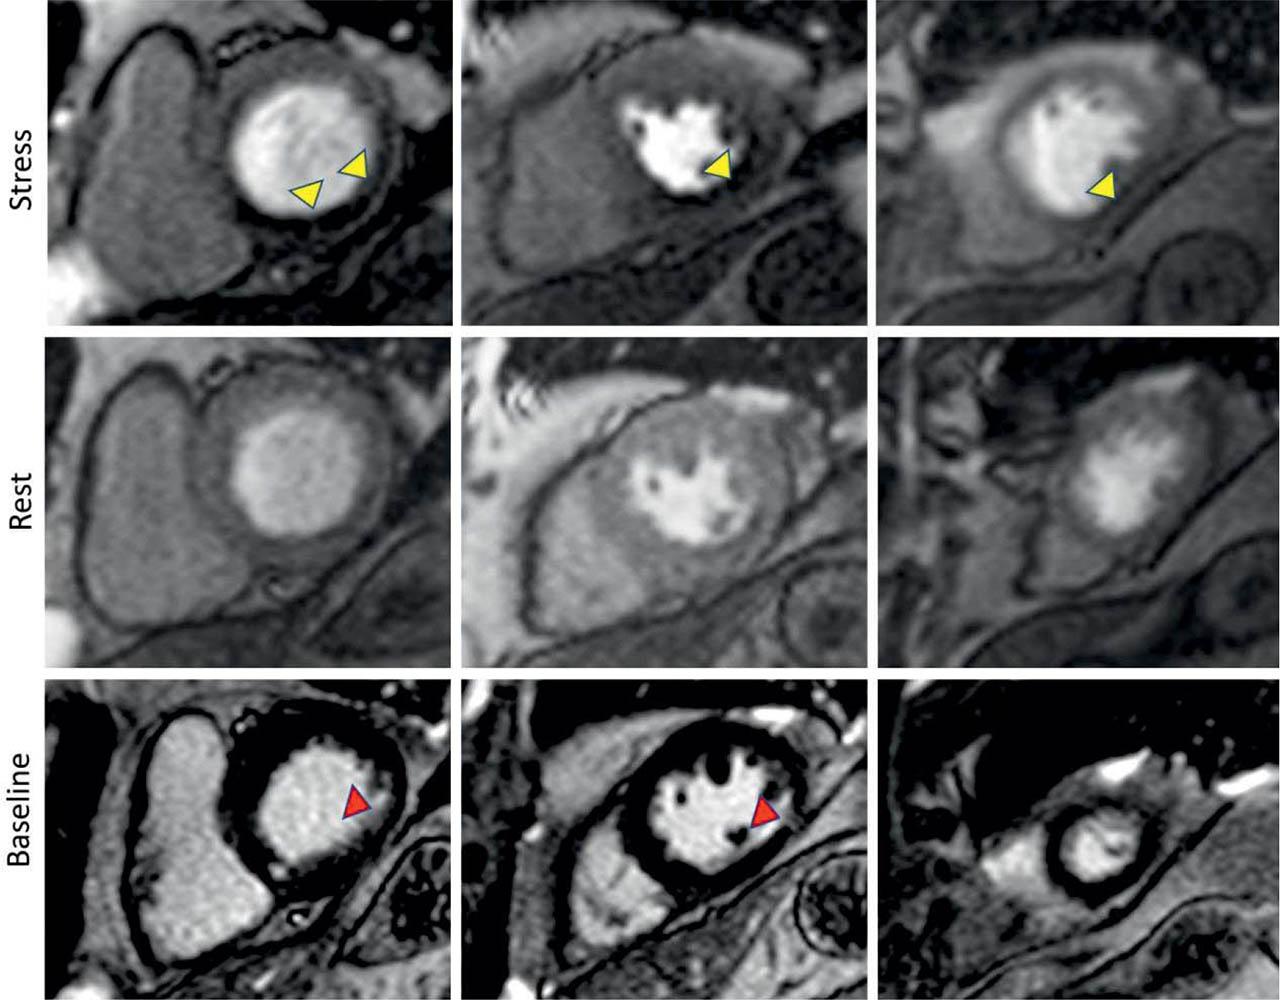

In 19 patients (15.83%), CMR contributed to a major change in diagnosis, such as: diagnosis of unknown previous MI, LV thrombus or myocarditis (Figure 4).

Figure 4

Stress Perfusion CMR in a 61-year-old patient with intermediate lesions on invasive coronary angiography, without a clinical history of myocardial infarction. Perfusion imaging acquired during adequate vasodilator stress (upper row) show a large perfusion defect in the right coronary (RCA) territory (basal infero-septum, inferior and infero-lateral walls, mid inferior and infero-lateral walls and apical inferior segment) (yellow arrowhead). The rest acquisition (middle row) shows no evidence of perfusion defect. Late Gadolinium imaging (lower row) shows a small subendocardial scar (hyperenhancement) in the RCA territory (red arrowheads). Of note, the stress perfusion defect extends well beyond the myocardial scar.

Among the non-invasive imaging techniques, CMR has the advantage of providing information on myocardial scars either ischaemic or non-ischaemic (Figure 4). Moreover, myocardial viability in infarcted territories may be appreciated by means of ischaemic scar transmurality. In our cohort 49 patients (40.83%) had ischaemic scars, and the concomitant information on viability contributed to the best decision for subsequent revascularization. In this context, CMR is the preferred imaging modality when concomitant information on myocardial ischaemia and viability are needed1.